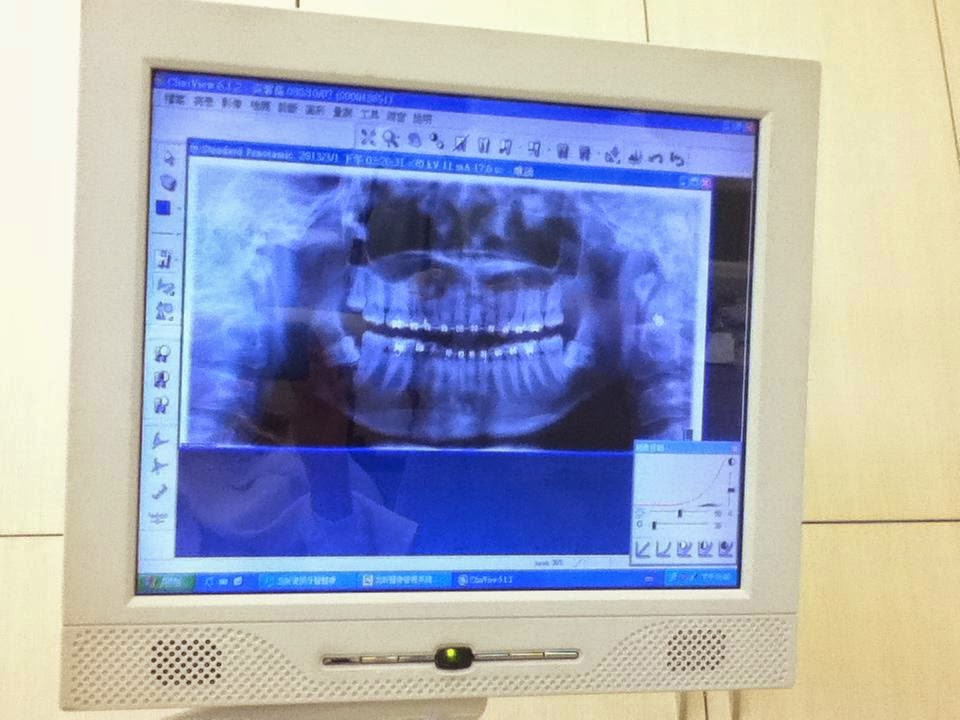

所以這本相簿的名字就這樣誕生了。(上圖是準備拆牙套前的X光照片,每顆牙齒不管用肉眼或是X光下看都是這麼整齊的排列著)